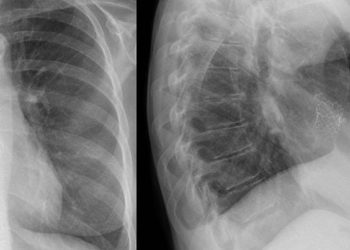

Steroidal mineralocorticoid receptor antagonists show little mortality benefit in patients receiving dialysis

1. Cardiovascular mortality and heart failure-related hospitalization were slightly less in the steroidal MRA group, though there was no statistical ...